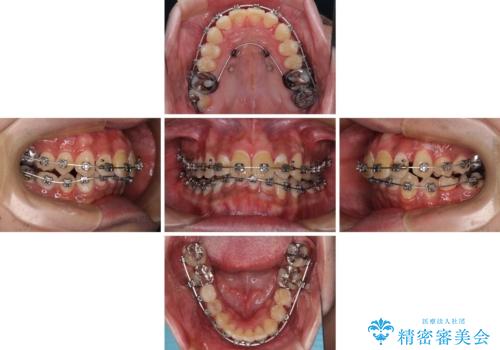

- 矯正装置

- メタルブラケット

- 治療期間

- 2年

下顎に対して上顎歯列が全体的に前方に位置しており、特に右側の奥歯の咬み合わせの前後のズレが大きいため、補助装置を用いて咬み合わせを改善することとしました。